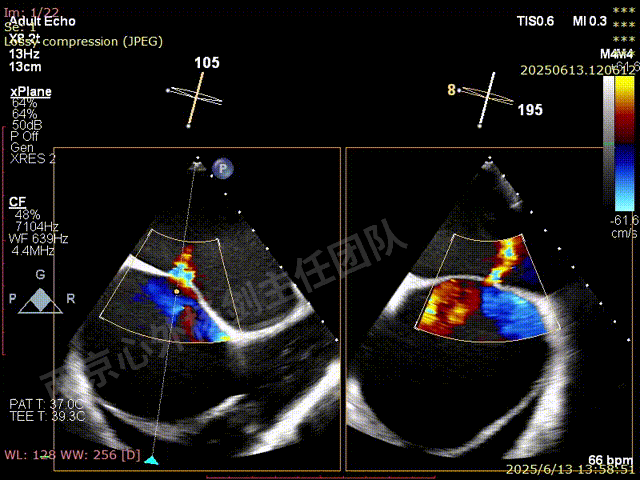

TAVR术后,全心增大,二尖瓣反流重度,三尖瓣反流重度。中量心包积液。左室严重增大,标准图像调整困难。主动脉瓣位带支架人工瓣膜瓣叶启闭正常,主动脉瓣位人工瓣上血流速度Vmax 148cm/s,PGmax 9mmHg,Vmean 86cm/s,PGmean 2mmHg, VTI 34.7cm,瓣周反流(轻)。估测肺动脉收缩压约49mmHg;左室收缩功能明显减低。LVEF:23%,EDV:364ml,ESV:221ml。

彩色血流示:二尖瓣反流缩流颈彩宽6.6mm,面积17cm²,容积30ml;二尖瓣瓣口面积6.6cm²,瓣环内径:左右径34mm,前后径34mm。2区瓣叶长度:前叶36mm,后叶20mm,叶环比1.6. 三尖反流面积17.2cm²,容积33ml,Vmax 291cm/s,PGmax 34mmHg。

TEER术前超声评估

二尖瓣后叶栓系严重,前叶相对错位,反流束沿2区分布广泛,2偏3区处存在反流。

反流宽度至少23mm,因影像调整困难,考虑实际反流更宽。